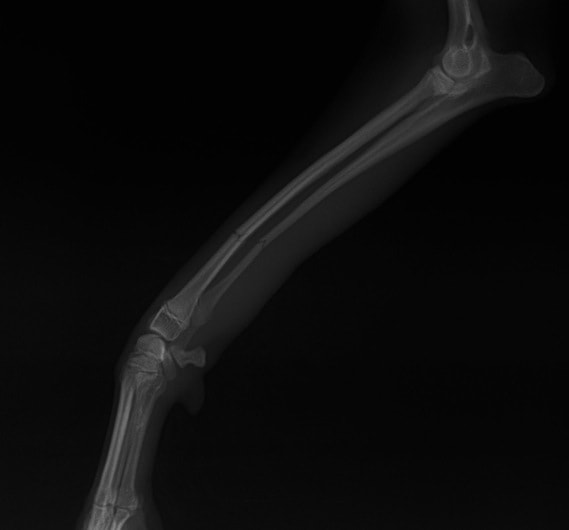

症例3:キルシュナーワイヤーのピンニングによる整復

ペルシャ猫 11ヶ月齢 雄

他院にて左大腿骨遠位の成長板骨折(salter-harrisⅠ型)が認められており、治療相談を目的として来院。当院にて、キルシュナーワイヤーを用いたピンニングにより骨折部位の整復を行いました。術後の経過は良好で、現在も経過観察中です。

術前レントゲン

術後レントゲン

機器

Arthrex社のターゲティングデバイスを用いてピンニングの位置を調整することで、確実な固定を行っています。当院ではこの手術器具以外にも、人の手術にも使用される様々な器具を導入し、手術精度を高め、また医療メーカーと新しい器具の開発、試作にも取り組んでおります。